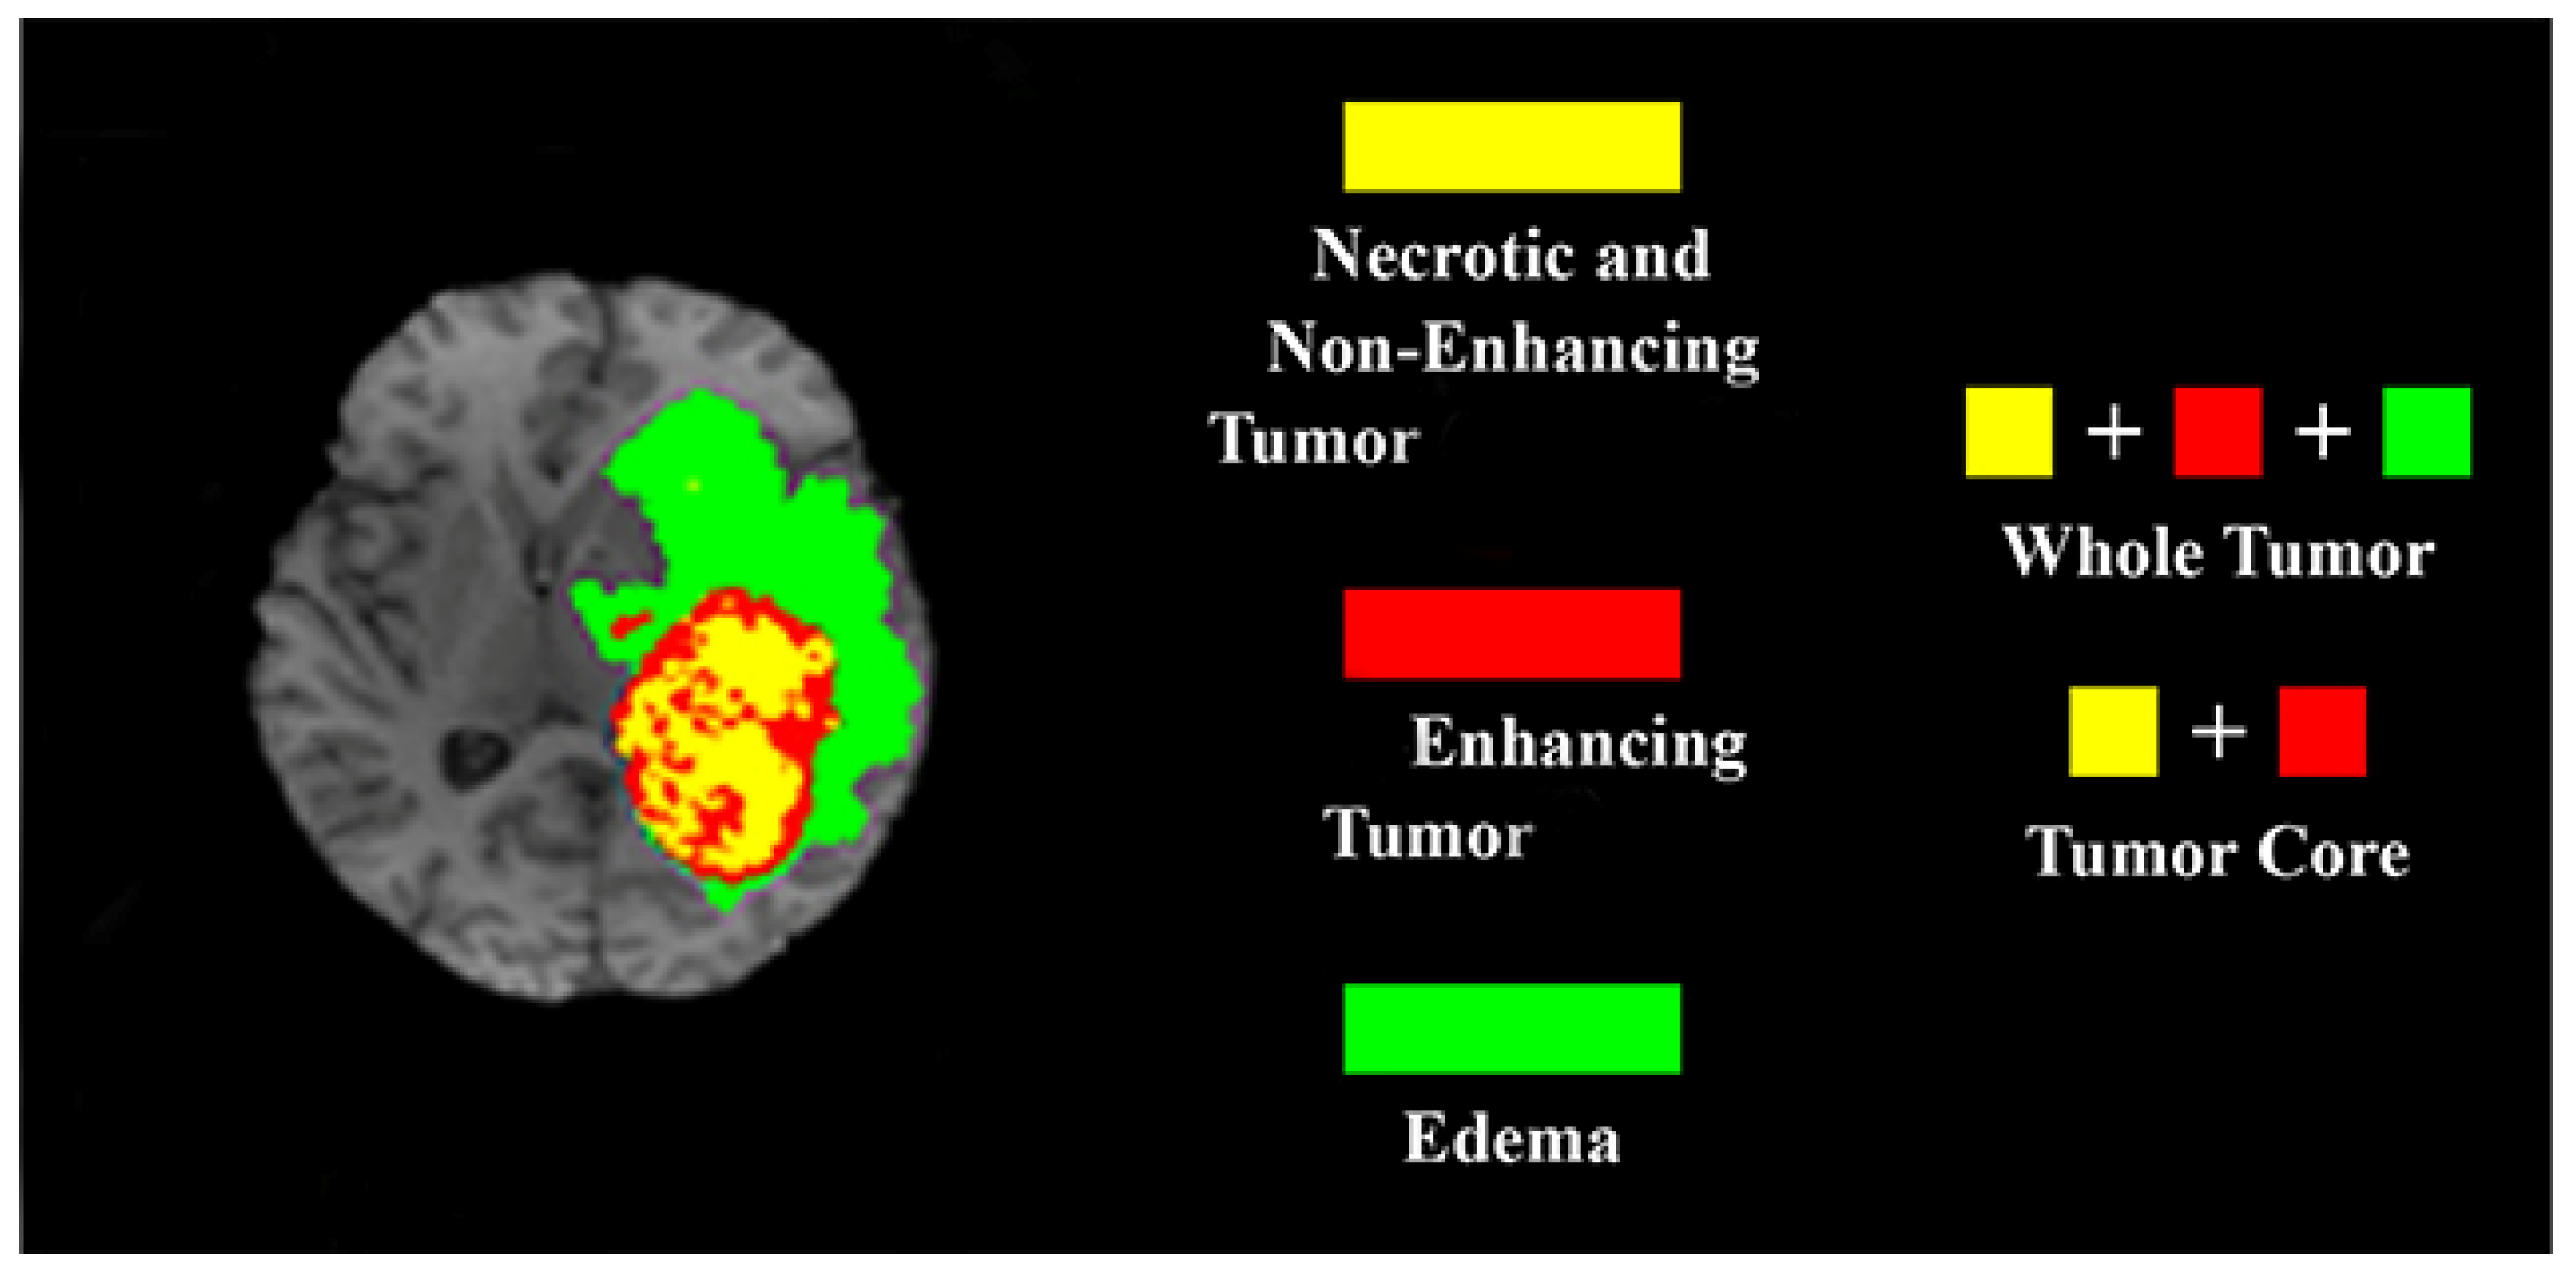

4.2. Experiments on the BraTS 2015 Database

4.2.1. Database Description